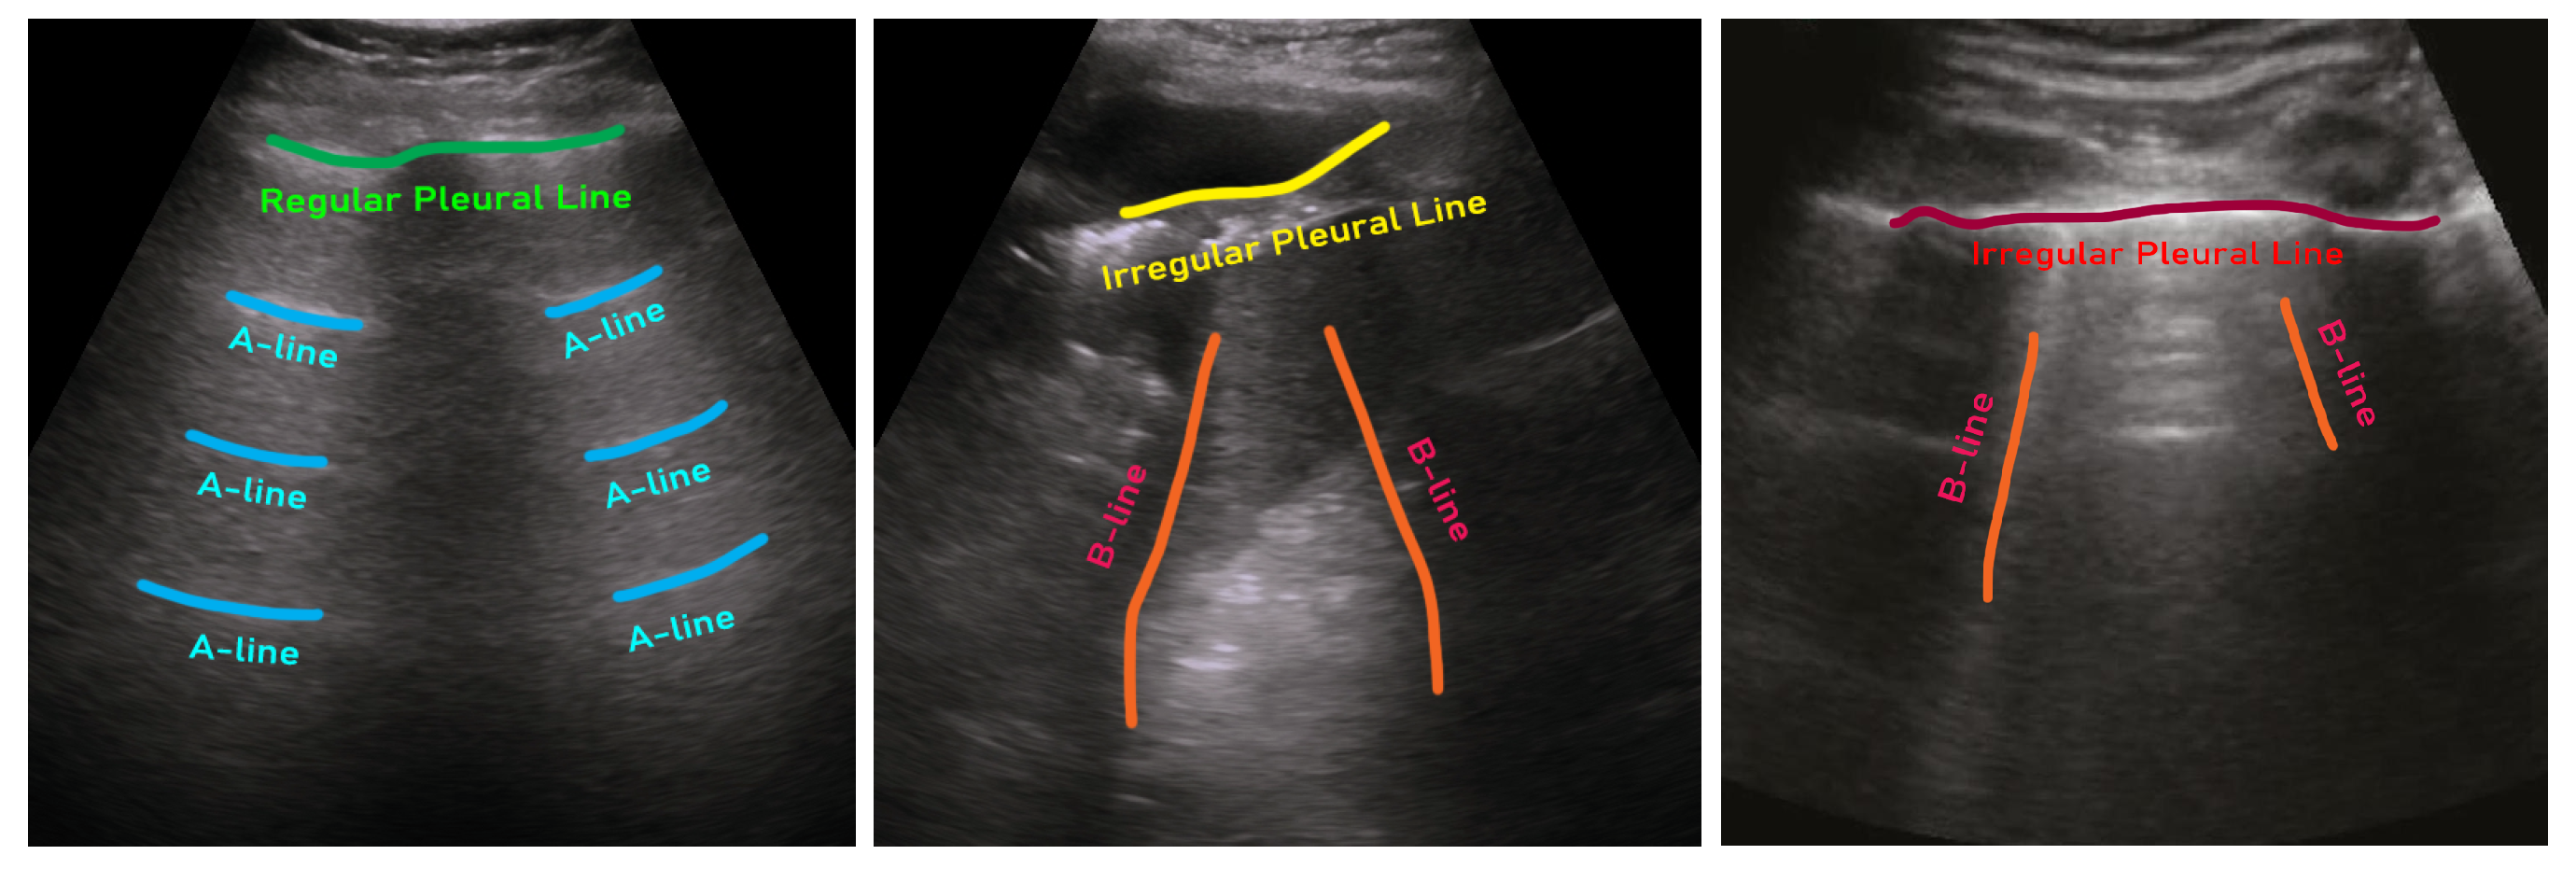

- ICLUS-DB: Soldati et al. [24] published an internationally standardized lung ultrasound acquisition protocol along with a four-level scoring scheme in March 2020. This dataset contains 277 ultrasound videos (consisting of 58,924 frames) of 17 confirmed COVID-19, 4 suspected COVID-19, and 14 healthy subjects. These data were collected at various clinical centers in Italy using various ultrasound scanners by either linear or convex probes. To evaluate the progress of pathology, this data consortium defined a four-level scoring system ranging from 0 to 3. Continuous pleural-line and horizontal A-lines indicate a healthy lung with a score of 0. Score 1 is tagged for initial abnormality when alterations in the pleural line appear. Score 2 is more severe than 1 and is associated with small consolidations in the lung. Score 3 is the most severe grade, which is associated with the presence of a larger hyperechogenic area below the pleural surface (i.e., white lung).